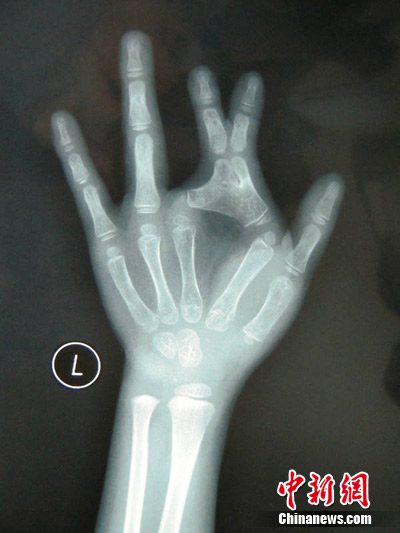

(Ecns.cn)--A 6-year-old girl in Chongqing was born with a deformed left hand, on which the first joints of her forefinger and middle finger stick together, resembling a pair of scissors.

The operation was quite challenging, according to Tian, "since the severely deformed finger joints had been sticking together."